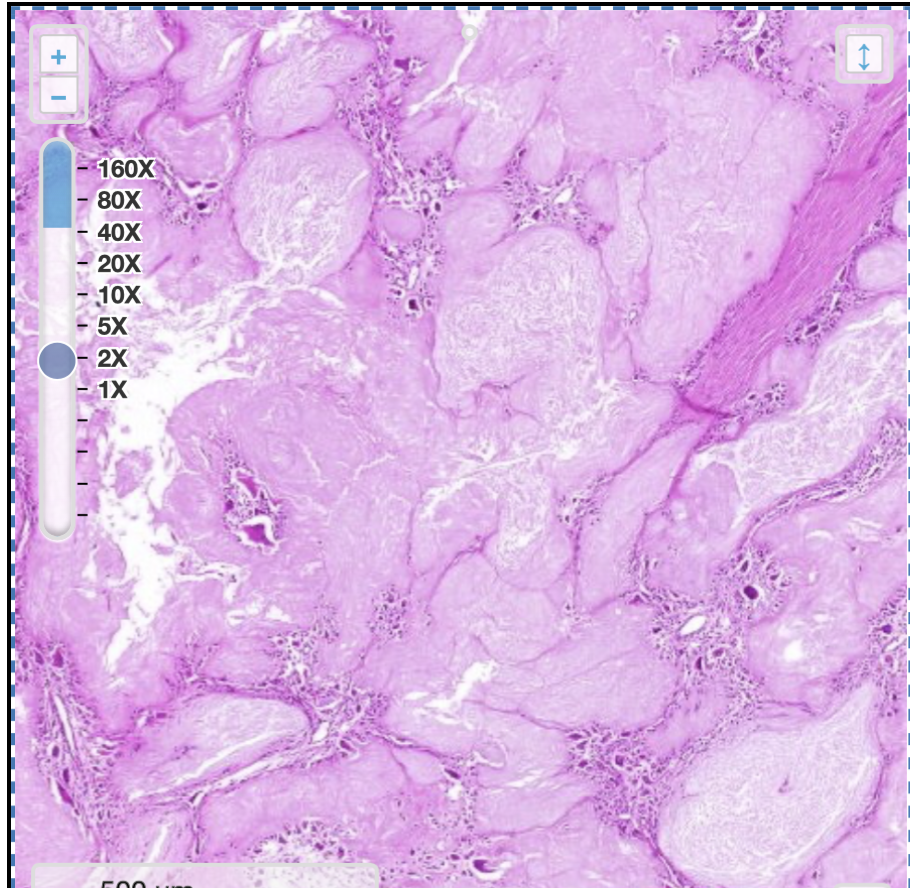

welk preparaat

tubulair adenoom in tractus digestivus

pathologische kenmerken tubulair adenoom in tractus digestivus

architectuur licht verstoord

te veel klierbuizen

kernen zijn groter en liggen apicaal

pseudostratificatie

hypocrinie

depletie van gobletcellen

minder mucussecreet —> minder helder cytoplasma

toegenomen aantal mitosen

wat zie je

tubulair adenoom

abnormale klierbuizen

hypocrinie (niet helder cytoplasma): door depletie gobletcellen en minder mucussecreet